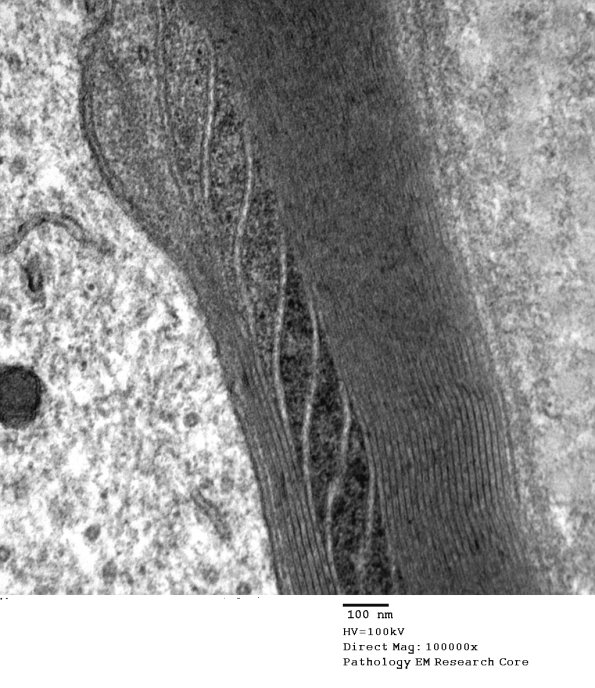

Notice in this case that the SLC ends at the adaxonal space adjacent to the axon. (Electron micrograph)